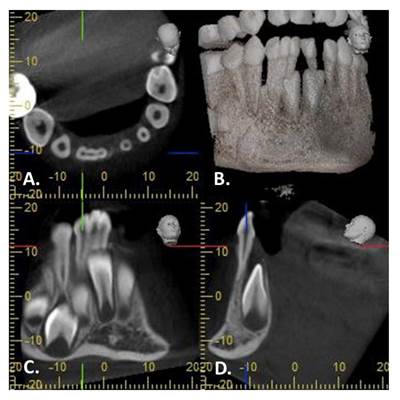

Se efectuó una tomografía hemimaxilar en un equipo J. MORITA MFG con un voxel de 0.125 mm; el software utilizado fue i-Dixel. El informe de la radióloga indicó: “se observa pieza 8.1 y 8.2 fusionadas, pero además se observa fusión con pieza supernumeraria, las tres piezas están unidas por las coronas y las raíces, y cada una presenta su cámara y conducto radicular”. En el corte axial se observa la fusión a nivel de dentina de las tres piezas; en el corte tangencial se aprecian las cámaras pulpares y los conductos radiculares de cada uno de los tres dientes fusionados. En el corte transaxial se observa la posición lingualizada del incisivo permanente inferior derecho (Figura 3).